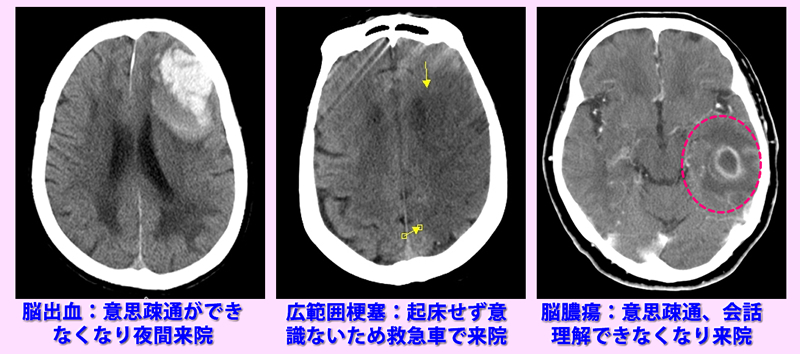

左側CT画像:夜間10時頃、意思疎通ができず、話がおかしいとのことで家族が連れて来院。前頭葉の出血認める。

CT中央画像:朝起きてこず、意識が無いことに気づき救急車で来院。

右CT画像:1-2日前から会話がおかしく、意思疎通ができないと受診。造影CTで脳膿瘍の所見で1週前の抜歯が原因と考えられる。

意識障害CT検査